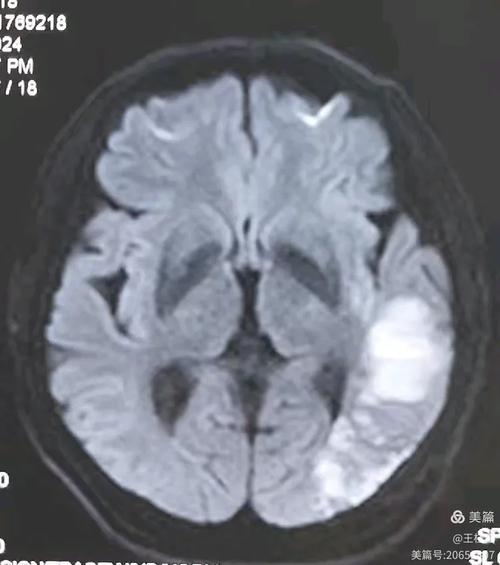

(图片来源网络,侵删)